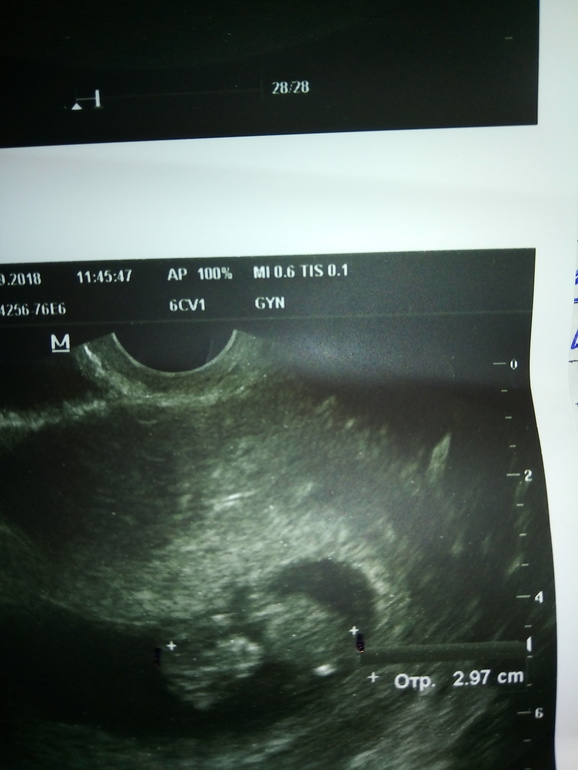

УЗИ, КТГ, доплер20 сентября была на узи, ктр 27 мм, а сегодня 26 сентября узи в другом месте 29.7 мм. Спрашиваю с тем, что правильно ли намерила узистка сегодня ктр, т.к. по фото видно, что стрелочка не на самом краешке головки. Или мне стоит бить тревогу? Чсс было 166, а сегодня даже не измерили, сказала только, что очень активный эмбриончик, сердечко видно как бьется.

2 фото сделано 26 сентября

Я понимаю про аппарат, но тут вопрос еще и в том, что я права или нет, что узист неверно установил курсоры или нет? Посмотрите на 2 фото

У вас на последнем фото ребёнок немного согнут. Плюс курсор верхний не у макушки стоит.

Со своим малышом и сравниваю. На фото посмотрите, пожалуйста. Разница почти в неделю, ну не может ведь он вырасти всего на 2.9 мм. И вопрос в том, правильно ли узистка навела курсоры на головку?